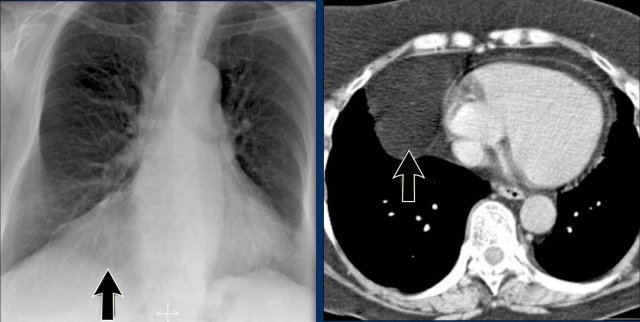

Hidden Areas (3): Pneumonia Below the Diaphragm

In this case, a pneumonia was primarily located below the right diaphragmatic dome (yellow arrow), within the posterior basal segment of the right lower lobe.

• On the lateral view, there is an increase in opacity over the lower thoracic vertebrae, indicating lower lobe consolidation (arrow).

• Again, image magnification may be necessary for adequate assessment.

Hidden Areas (4): Retrocardiac Opacity

Initial review of the CXR reveals a subtle increase in density in the retrocardiac region (blue area), which requires careful attention.

• This was confirmed to be a left lower lobe pneumonia.

• Always correlate with the lateral view, where consolidation in the lower thoracic spine region is a key clue.